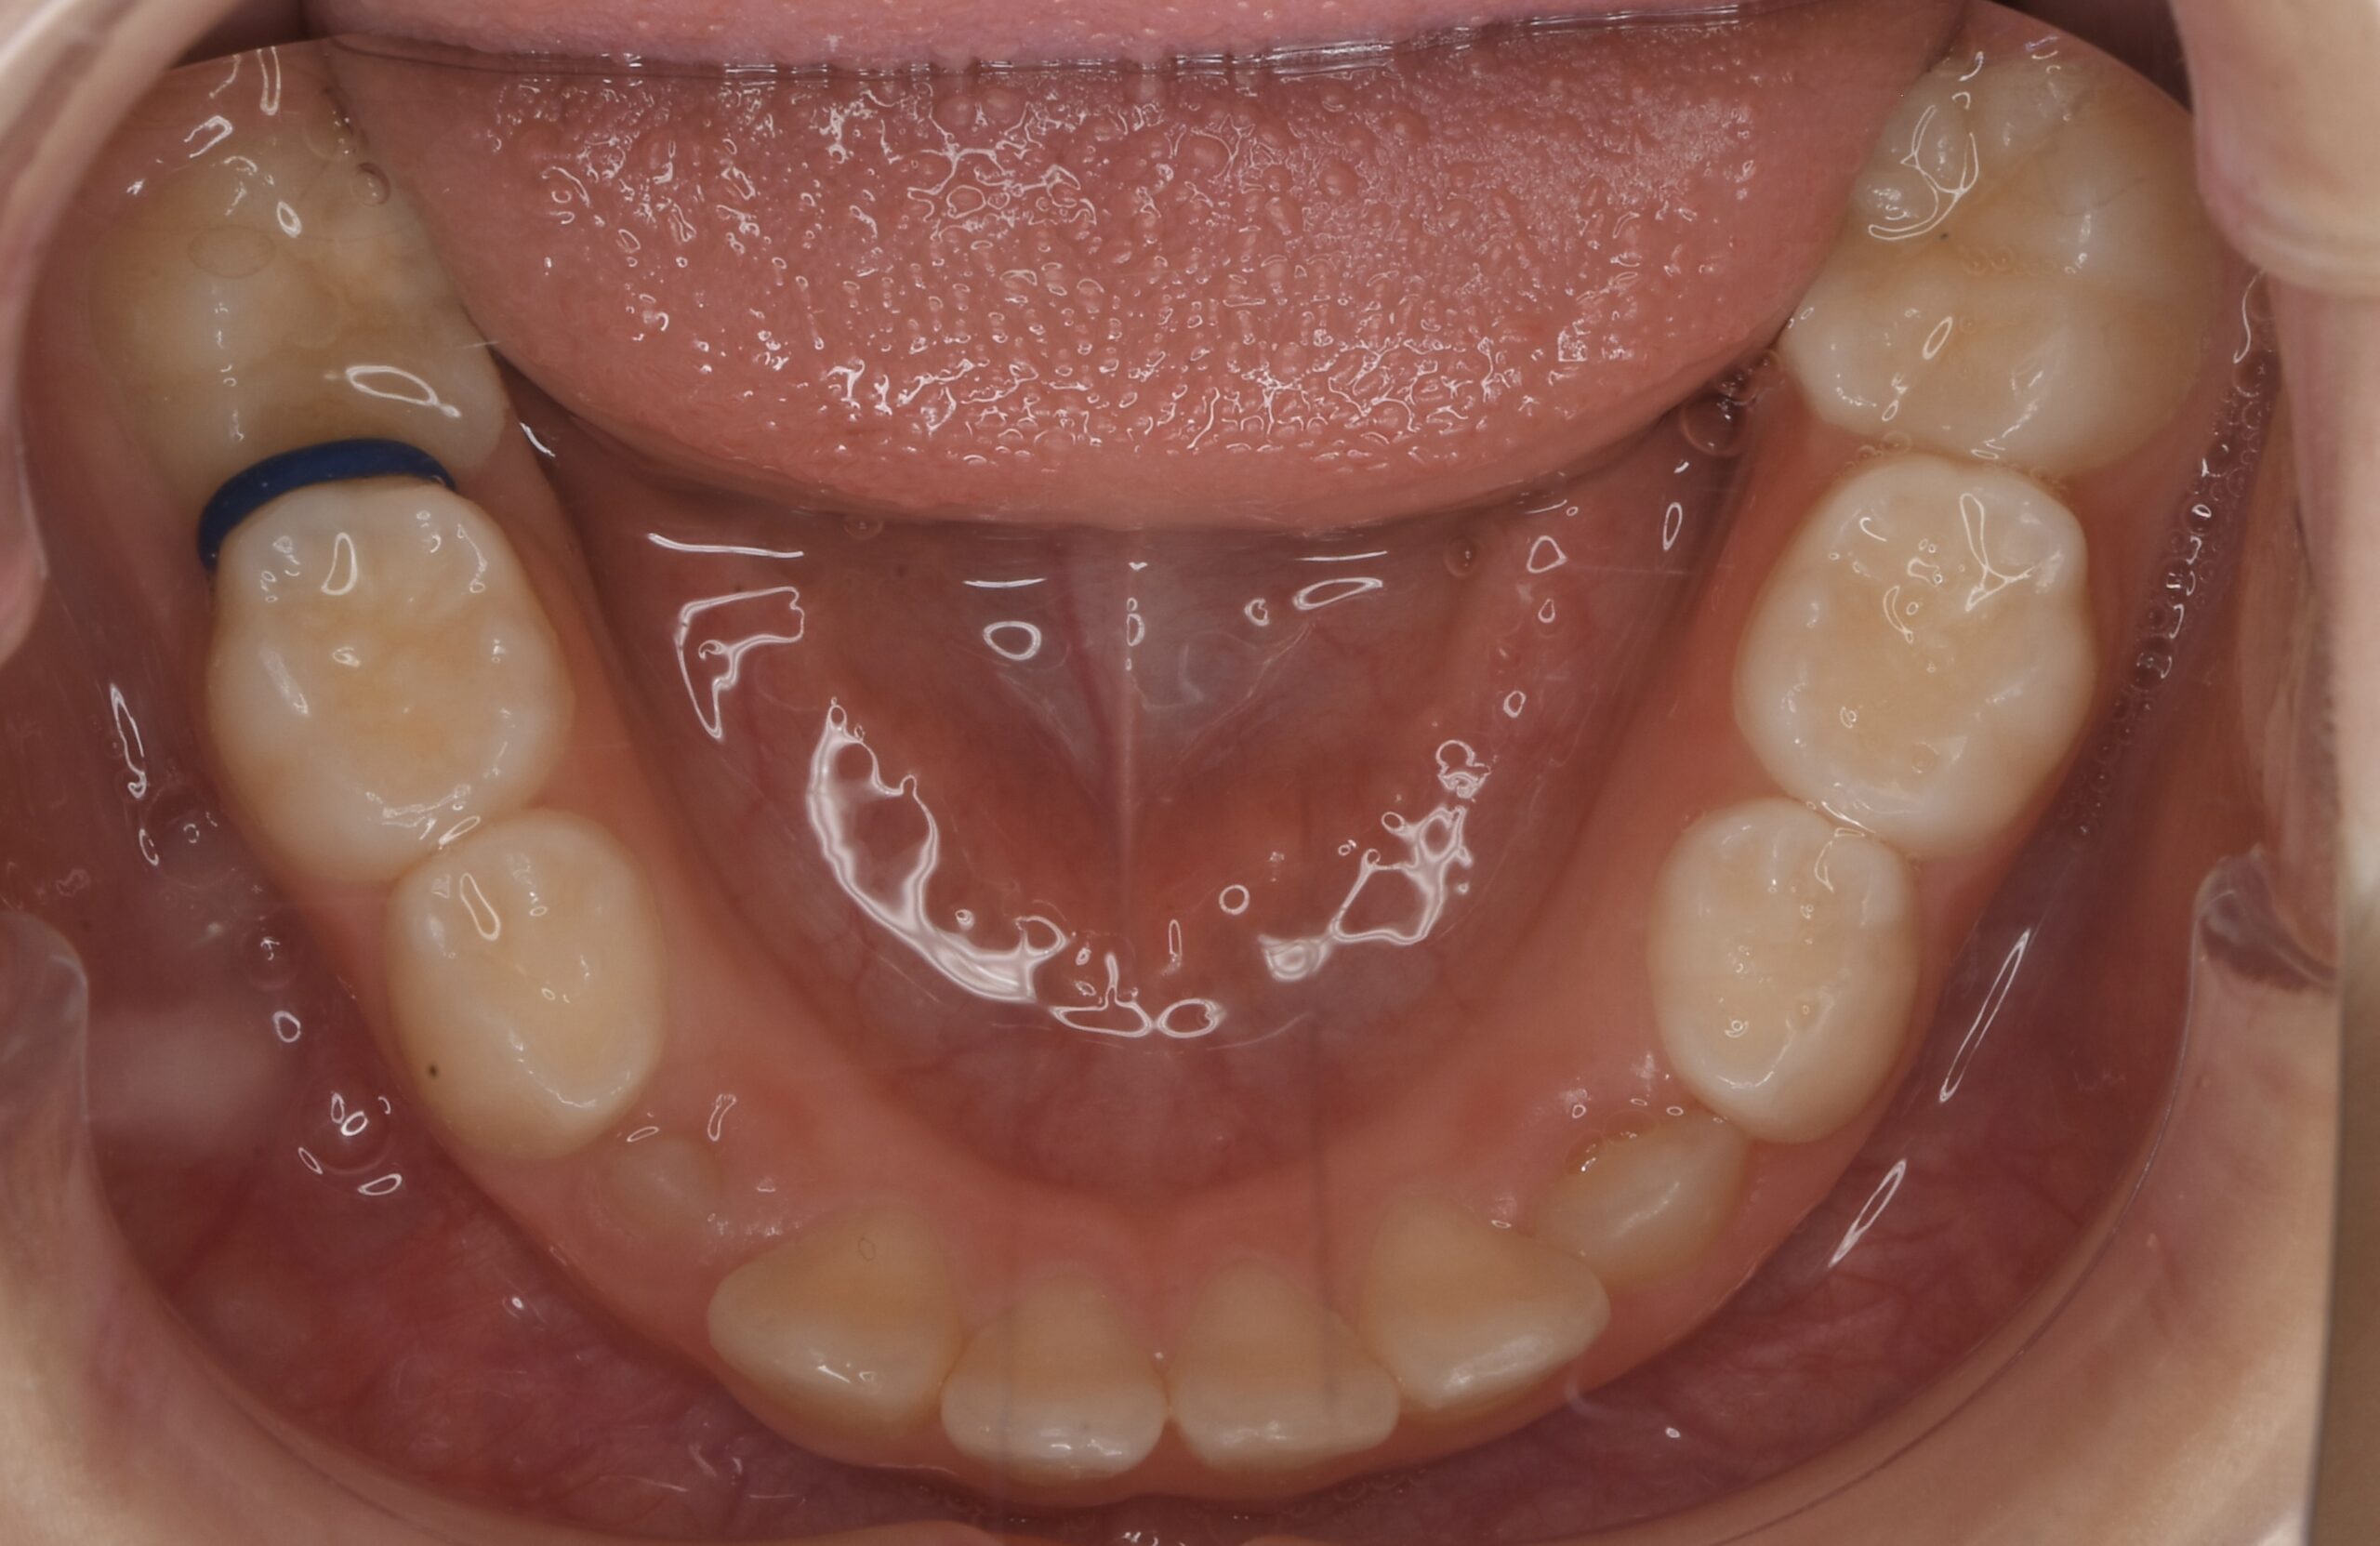

- BEFORE

| 治療内容 | 永久歯がきれいに並ぶスペースが不足していたため、上あごの成長を促す顎顔面矯正装置(拡大装置)を使用しました。 現在、第2大臼歯の萌出経過を観察中です。 永久歯の生え変わりに合わせて歯並びや噛み合わせを確認しながら、必要に応じて継続的な管理を行っています。 false |

| 使用装置 | 顎顔面矯正装置(拡大装置) false |